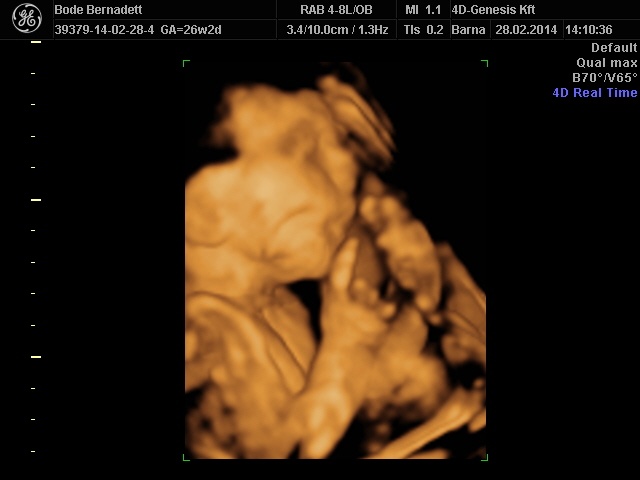

És már biztosan nagyon szépek lesznek a képek, alig várom, hogy feltöltsd, és láthassam. ![]()